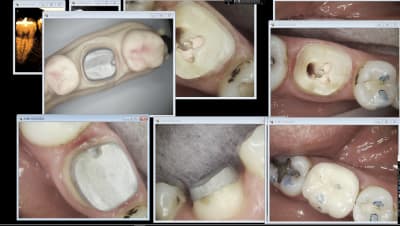

putain , m' en parles pas , j'suis degouté .

ça encore ç est rien :-)

et tu crois qu ils sont brillants pourquoi ? pcq ils ne savent pas faire 1 forme qui va bien .donc je retaille de longue .

par exemple sur celui là dont tu parles , lorsque je l ai retaillé en bouche , le liseré est apparu .

mais y a plus rigolo !!!

ç est que pour une fois que je ne l ai pas renvoyé ( il rentrent tous bien ,ce n est pas le probleme , hein ) ,voilà ce que j ai reçu avec l emax

mg 1536 lsqpqq - Eugenol

figures toi qu il n'avait pas prévu assez de place pour sa couronne .

" mais pourquoi ? , ç est toi qu'a fait l 'IC , à ce point t'es abruti ?? "

"" ha yesais pas , a comprends pas ""

même pas je lui en veux , 30 ans que ça dure je dois être maudit de l IC , j vois qu'ça